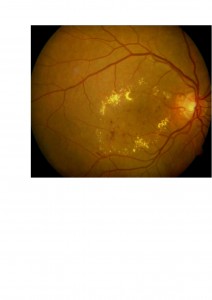

2. El tratamiento con láser puede conseguir mejorías significativas en determinados tipos de edema macular diabético (el denominado edema macular focal que se caracteriza por la abundancia de exudados lipídicos en la mácula). Os mostramos un ejemplo en el que podéis comprobar cómo desaparecen los exudados lipídicos amarillentos después de la fotocoagulación de la mácula.